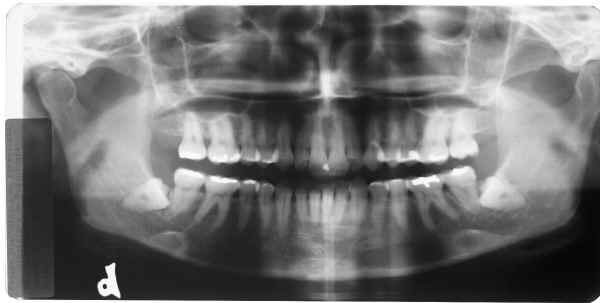

RX superior esquerdo

início

Rx superior direito

Rx inferior esquerdo

Rx inferior direito

Qual destes lados não foi editado?

Responda, justificando, e receba a resposta com as fotos originais!

Matematicamente a probabilidade de erro na 1ª resposta é igual a 75% = 3/4 x 100

Matematicamente a probabilidade de erro na 2ª resposta é igual a 50% = 1/2 x 100

Não aposte sua prova jurídica nisto, responda e verás!